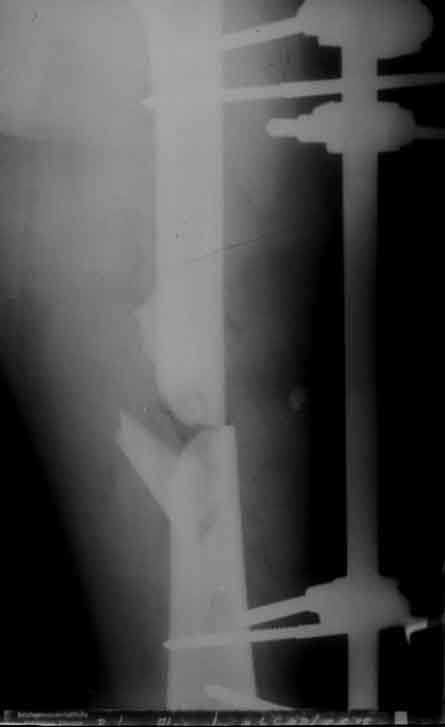

Offene Oberschenkelfraktur

Rö.Bild vor und nach der Stabilisierung mit Hoffmann 2 Fixateur in der "free Pin-.placement" Technik.